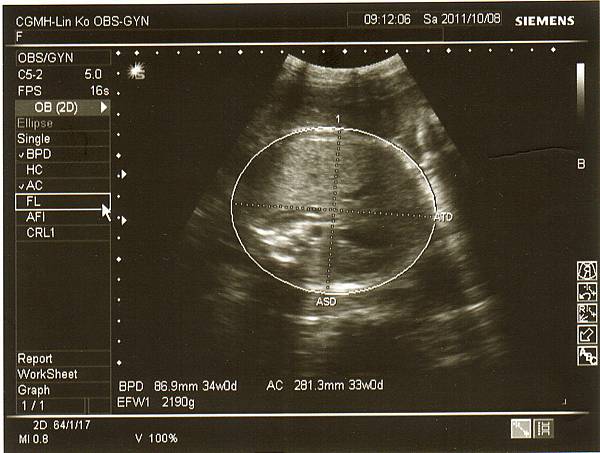

但是寶寶也才增加約200克,現在寶妹約2190克,

醫生說小了一些些,不過羊水量和心跳都很正常,